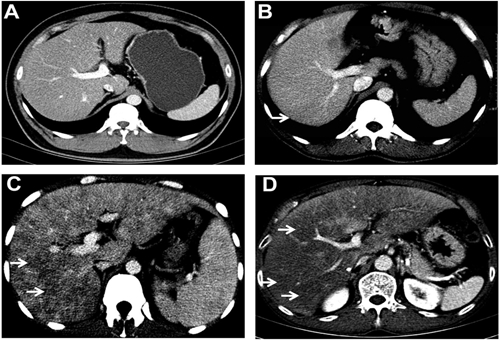

上腹部增強(qiáng)CT

例如當(dāng)我們平掃時(shí)發(fā)現(xiàn)肝臟上發(fā)現(xiàn)一個(gè)低密度影,但是又不能確定這到底是一例肝癌、肝囊腫或者肝血管瘤或其他病變時(shí),增強(qiáng)CT就派上了大用場(chǎng)!通過(guò)三期掃描,研究其血供情況可以判斷出病變種類。